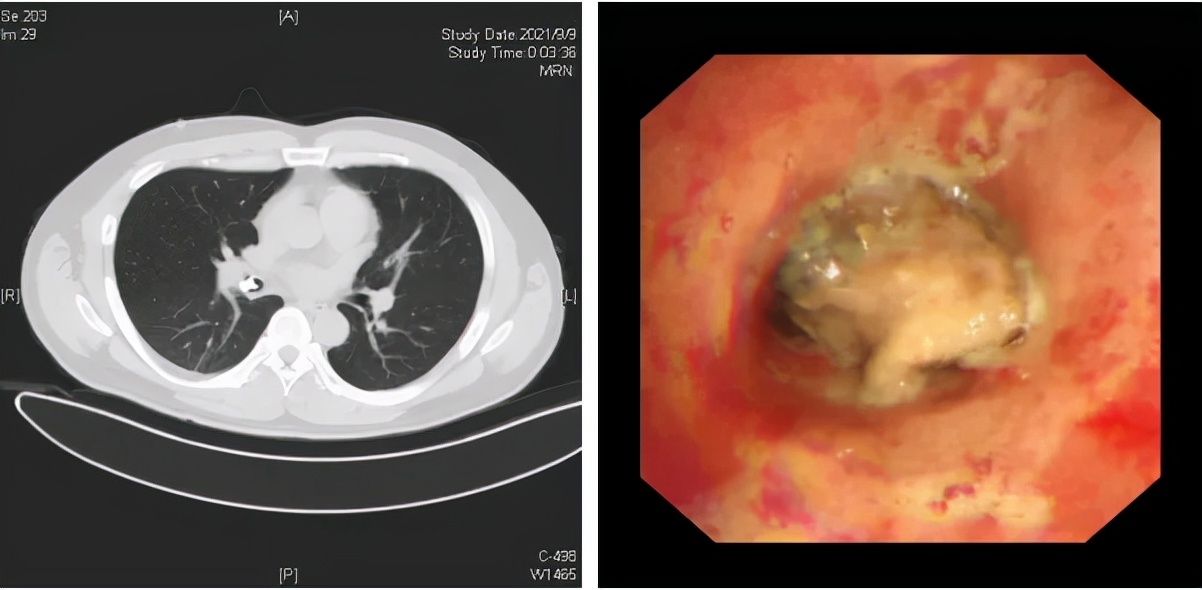

图2:支气管异物

图2,34岁的李先生晚上自感鼻腔内有异物,不慎吸入,随后出现持续性剧烈干咳、少量咯血、憋气、呼吸时自感“气管内有异物”。李先生赶紧来到清华大学附属北京清华长庚医院急诊科就诊,胸部CT检查显示右侧支气管内高密度异物影。急诊医师立刻联系呼吸与危重症医学科紧急会诊,考虑气道异物较大,立刻为患者联系安排支气管镜检查,镜下可见患者右中间段支气管内有一灰褐色异物,呈现不规则形态,几乎完全阻塞了支气管腔,与支气管嵌顿紧密,远端气道无法窥及。后经支气管镜取出,卡在气管的异物终于露出了真面目——竟然是一块肉骨头!而患者也不知道它是何时呛入气道内的。

取出的异物——肉骨头